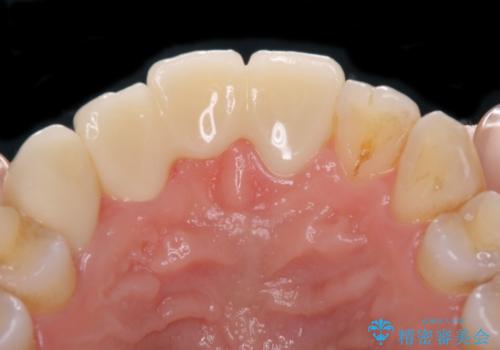

補助装置により上顎歯列を遠心移動させたため、非抜歯でしたが口元の突出感をある程度改善させることができました。

欠けてしまった前歯もオールセラミッククラウンにて自然に補綴することができました。